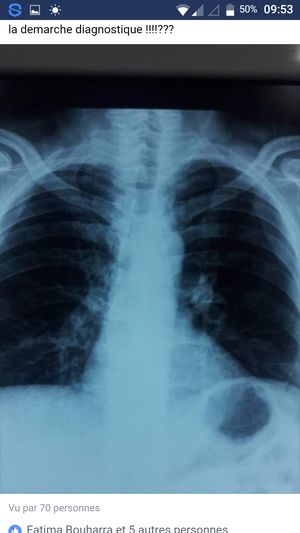

Âge 60 years Retrostenal pain Abondant sputum Thoracic compression